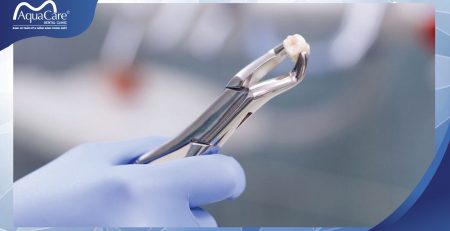

Khi nào nên nhổ?

Nếu chiếc răng khôn của bạn mọc nghiêng, sâu nhiều thì việc nhổ bỏ sẽ được tiến hành để bảo vệ cho răng bên cạnh. Răng khôn bị sâu nhiều tức là phần thân răng đã bị vi khuẩn tấn công, nếu không nhổ bỏ sẽ dễ gây lây lan sang các răng bên cạnh.

Ngoài ra, trường hợp răng số 8 bị sâu thì đây còn có thể là nguồn đưa vi khuẩn truyền nhiễm từ nướu răng gây lây nhiễm cho tim và thận. Việc nhổ bỏ những chiếc răng không còn đảm bảo được chức năng ăn nhai này chính là cách để phòng tránh bệnh răng miệng hiệu quả.

Có nhiều bạn lo lắng, nhổ răng khôn ảnh hưởng đến dây thần kinh. Tuy nhiên việc điều trị này không ảnh hưởng đến dây thần kinh đâu bạn nhé!

Việc xử lý răng khôn bị sâu không phải đơn giản, nếu thực hiện ở cơ sở vệ sinh kém có thể bị nhiễm trùng. Nhiễm trùng hậu phẫu là một biến chứng khi nhổ răng số 8 diễn ra khá phổ biến.